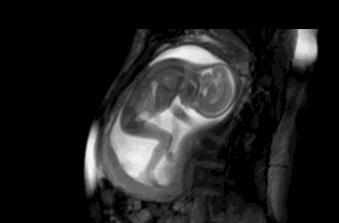

其实小家伙很小的时候就已经开始“闹腾”了:妥妥的一个运动健将!

小碎步向前缩,撅着小屁股用力一蹬,身体向后滑去——“母胎版蛙泳”动作很标准嘛!

不行,刚才的动作不够标准,再来一次!

不过,力气好像还是太小了,算了,休息休息再说~